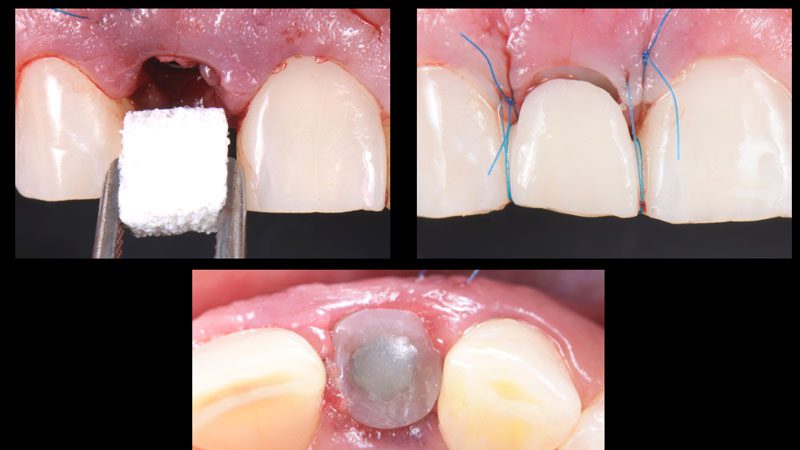

Hình 3. Sau khi đi mũi khoan đầu tiên và đặt pin định hướng (guide pin) để xác định lại hướng và vị trí Implant.

Hình 4. Đặt Implant Straumann BLT 2.9 x 14 mm.

Hình 5. Thực hiện một trụ Healing cá nhân bằng nhựa composite để duy trì cấu trúc mô mềm xung quanh.

Hình 6. Hình ảnh Healing cá nhân sau khi thực hiện.

Hình 7. Ghép mô mềm (lấy mô từ khẩu cái) bằng kĩ thuật đường hầm (tunneling technique).

Hình 8. Ghép Collagen BioOss vào vùng thiếu hổng, đặt trụ Healing cá nhân. Sau khi gắn phục hình tạm (cầu dán Maryland) thì thêm 2 mũi khâu treo xung quanh để nâng đỡ cho mô ghép.